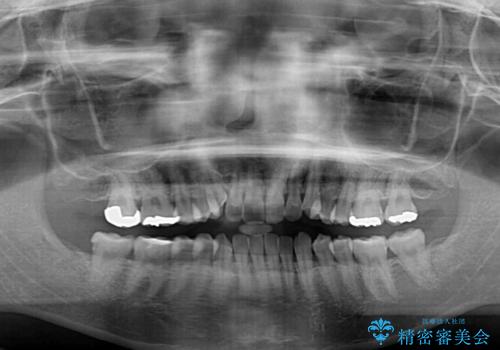

- 上顎の八重歯と全体的なデコボコを気にして来院された患者様です。

口元の突出感はなかったため非抜歯矯正での対応となりますが、八重歯を改善する際に上顎前歯が前突する可能性があったため、上顎臼歯部にアンカースクリューを使用して、歯列が前方に転位しないようにすることとしました。

また舌のトレーニングを行うことで、上顎前歯の突出予防や上下前歯に隙間ができなくなるようにしました。

ワイヤー矯正でもインビザラインでも対応可能でしたが、上顎歯列が前方位であるときには、ワイヤー矯正の方がより良い仕上がりとなる可能性が高いため、ワイヤー矯正をおすすめいたしました。